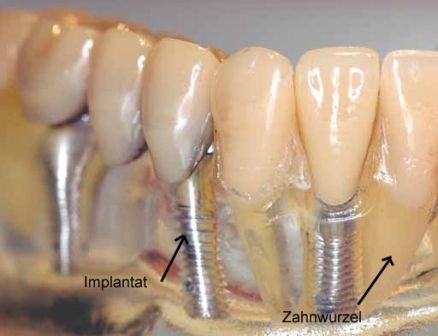

İMPLANT NEDİR? İmplantlar, diş kökü şeklinde titanyumdan hazırlanmış, çene kemiğine küçük bir operasyon ile yerleştirilen suni diş kökleridir. Titanyum doku dostu bir malzemedir. Kemik ile özel bir bağ oluşturarak yerleştirildiği yere, hücresel olarak tutunur. Bu tutunma tamamlandığında (2-6 ay) üst yapı dediğimiz protezi hazırlama işlemine geçilir. Günümüzde implantlar tartışmasız olarak doğal dişe en iyi alternatiftir.

Endosteal implantlar - bu implantlar, cerrahi yöntemle, çene kemiğine direkt olarak implante edilirler. Çevredeki dişeti dokusu iyileştikten sonra, orijinal implanta bağlantı sağlayacak materyali takmak için ikinci bir operasyon gerekir. Son olarak, yapay diş (veya dişler) tek başına veya köprü ya da protez üzerinde grup halinde implanta takılır.

Subperiosteal implantlar - bunlar, dişeti dokusunun hemen altındaki çene kemiğine takılan metal bir çerçeveden oluşurlar. Dişeti iyileştiğinde, çerçeve çene kemiğine sabit hale gelir. Çerçeveye takılan materyaller, dişetlerinden dışarı çıkar. Endosteal implantlarda olduğu gibi, yapay dişler, daha sonra implantalara monte edilir.